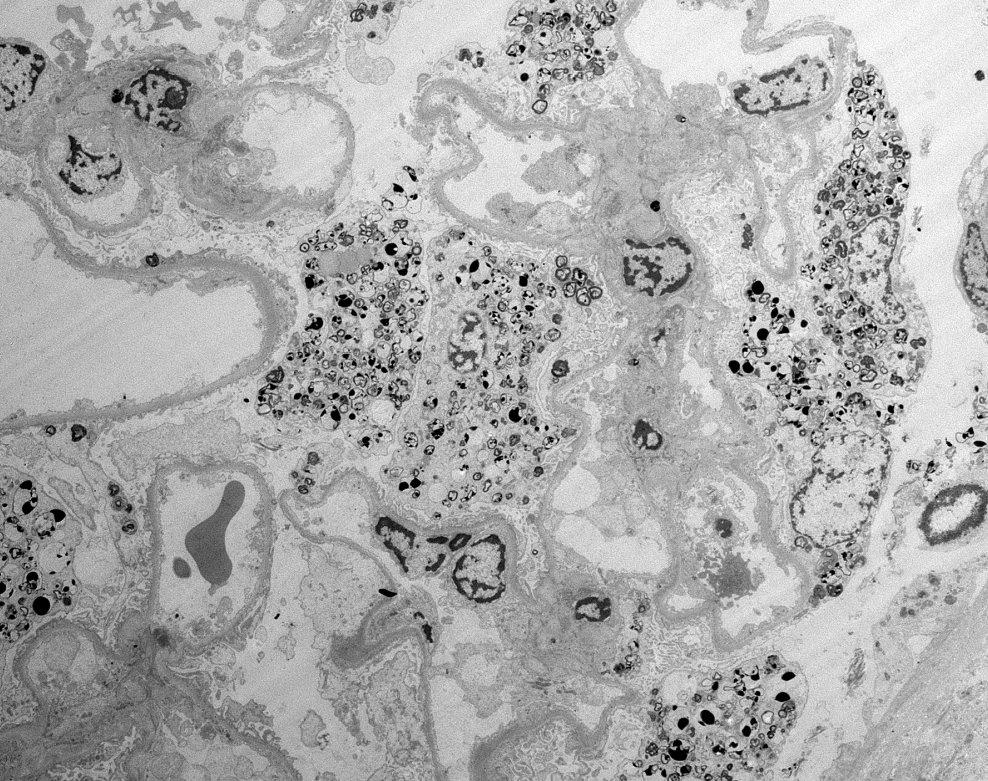

Mini case-series of crystal-storing histiocytosis (CSH) affecting predominantly glomerular loops with detailed literature review of renal CSH, images of one of the cases are depicted below, authors.elsevier.com/c/1Zh4S3uV~y8B…